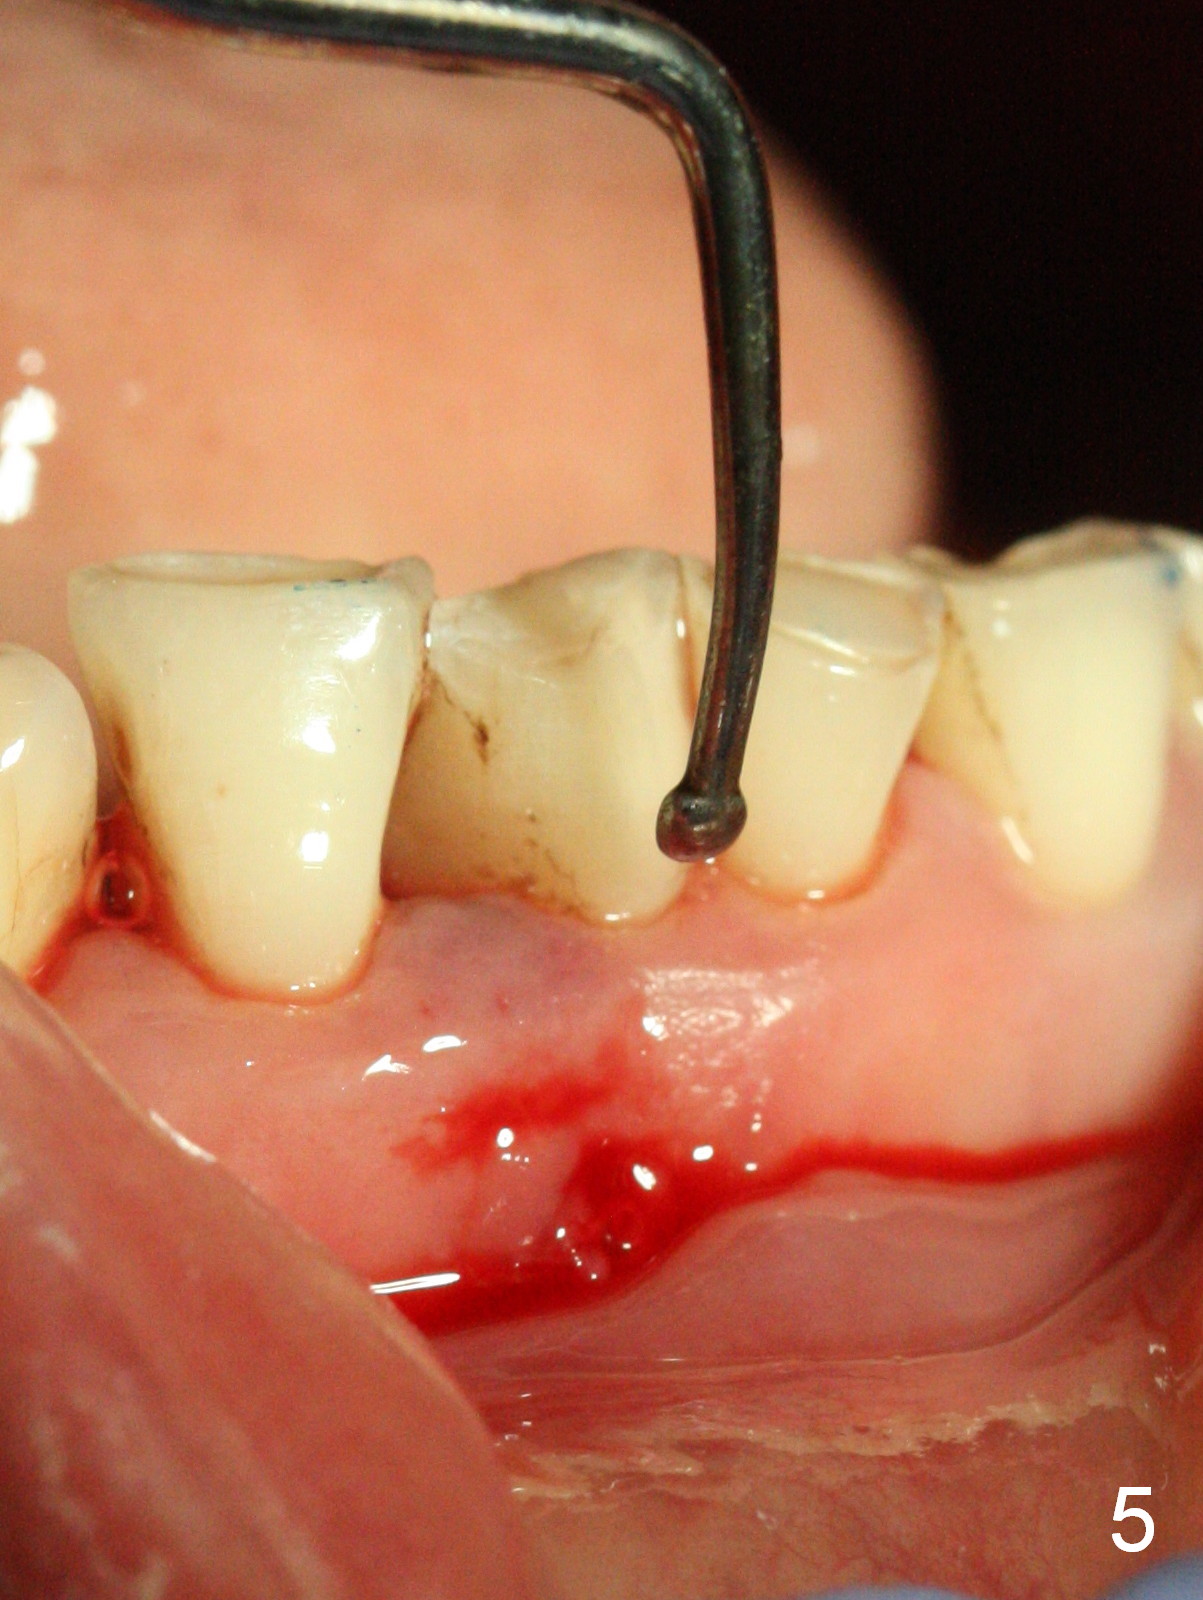

A 45-year-old man has had a chronic fistula associated with the tooth #25 (Fig.1). There is purulent discharge sometimes. After debridement with hand files #10-20 and rotary one 30/06, a master cone 30/.06 is inserted incompletely (Fig.2). After rotary files 30/.08 at 16.0 mm and 30/.10 at 15.0 mm and hand files 10-20 at 17 mm, the master cone is apparently inserted to the WL. With application of Endo Sequence Sealer (syringe), the master cone is reinserted (Fig.3). When the rubber dam is removed, the sealer is found to have expelled from the fistula. With an endo curette (Fig.5), the sealer is removed from the deepest portion of the sinus tract (apex of the tooth). What do you want to know the outcome of the supplementary surgical maneuver? The sealer is gone (Fig.6). The immediately supplementary treatment avoids a separate apicoectomy. No fistula is noted <2 weeks postop (Fig.7). The attrition is due to #8 and 9 veneers, fabricated 8 years earlier. The tooth #24 is symptomatic with loss of incisal composite nearly 4 years postop (Fig.8 <). After 30/.04 gutta percha (GP) try in (Fig.9), RCT is finished without accessory GP (Fig.10).